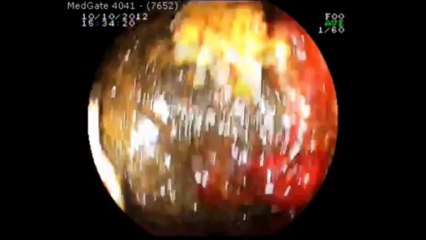

br Prof. Dr. Kayıhan Günay br MR Dekografi işleminin video görüntüleri.